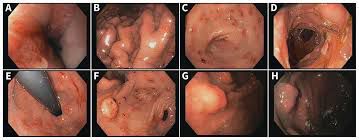

Zollinger-Ellison syndrome (ZES) refers to excessive production of acid and its manifestation secondary to gastrin-producing tumors. These tumors may be present in proximal part of small intestine or pancreas or both. These tumors are also called gastrinomas. Excessive gastric acid secretion results in peptic ulcers. Individuals with multiple endocrine neoplasia type 1 have increased risk of developing ZES. The condition is more common in men aged between 30 to 50. The symptoms of ZES are: - Nausea - Vomiting - Burning abdominal pain - Heartburn - Weight loss - Diarrhea - Black stools secondary to intestinal bleeding Proton pump inhibitors are effective in relieving the symptoms. Surgery is also done in some cases. Reference: https://www.hopkinsmedicine.org/health/conditions-and-diseases/zollingerellison-syndrome Image via: https://www.cmaj.ca/content/191/49/E1358